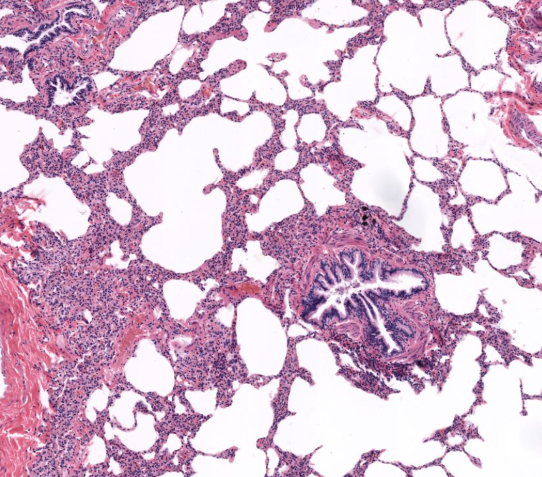

(organ)

lung

bronchiole cartilage of lung

terminal bronchiole of lung